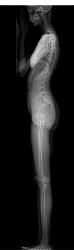

当院では、脊椎、腰、股関節の形体・配列の評価を行うことができるX線撮影装置「sterEOS(イオス)イメージングシステム」を県内で初めて(国内で3機目)導入しており、この装置では、通常のX線撮影と比較して50%、CT撮影と比較して95%放射線量を低減した撮影ができます。また、マイクロドーズモードを使用することで、経過観察の小児や、経過治療中に頻回の撮影を必要とする疾患の患者さんに対し、さらなる放射線被ばく低減を可能にします。

sterEOSイメージングシステム

このEOSの画像検査により、低被爆で弯曲のタイプ・進行具合を確実に診断出来るので、治療方針の決定に大いに役立ちます。